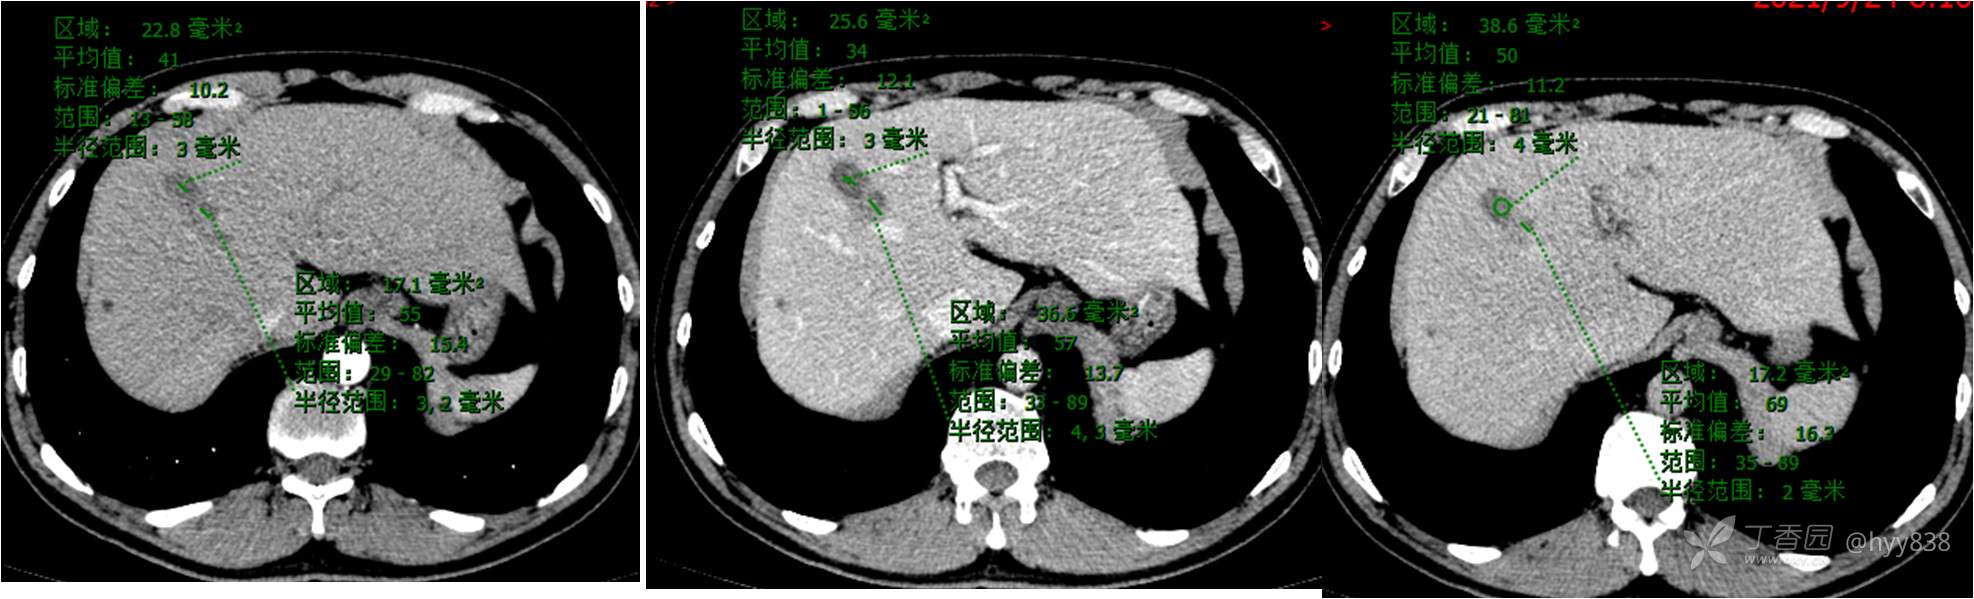

腹部CT平扫

增强(常规三期)